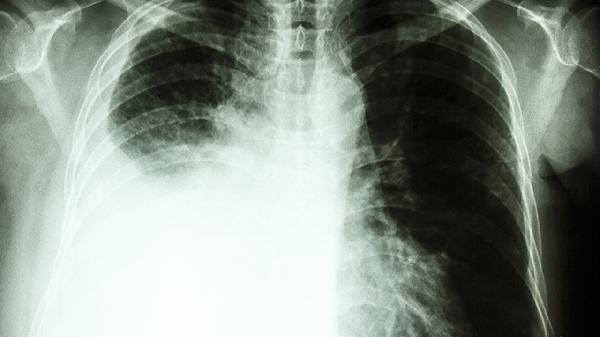

- 6 右侧大量胸腔积液是癌症吗